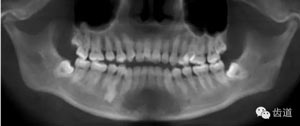

第三磨牙存,18與28牙冠小,38、48前傾阻生

中線不齊。未見(jiàn)明顯牙槽骨吸收。

下頜后縮為主要特征的骨性II類,高角,前牙開(kāi)合,上前牙略唇傾,雙側(cè)下頜升支及髁狀突不對(duì)稱,右側(cè)較左側(cè)粗壯,左側(cè)髁狀突外斜面曾有吸收,但現(xiàn)骨白線與皮質(zhì)骨已比較連續(xù),上呼吸道正常。上

頜第三磨牙牙冠較小。

牙與牙弓:25腭側(cè)完全錯(cuò)位導(dǎo)致26前移,上牙列重度擁擠,下牙列中度擁擠,上牙弓尖圓形,下牙弓卵圓形,第三磨牙牙胚存,18與28牙冠較小且形態(tài)不良

治療后曲面斷層片